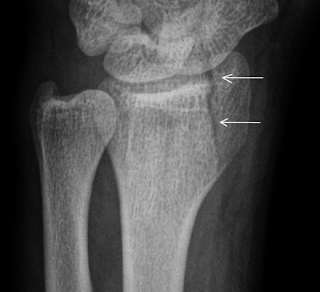

With associated distal radius fracture: Impaction between ulnar styloid tip and triquetrum that is seen in patients with excessively long ulnar styloids or ulna positive wrists. The ulnar styloid process is a bony protrusion at the end of the ulna, close to the hand. However, large ulnar styloid base fractures or displacement over 2 mm may require open reduction and fixation of the ulnar styloid fracture to achieve druj stability due to proximity of major druj stabilizing ligaments. Ulnar styloid fractures are frequently ignored in the treatment of wrist fractures in children. Does an untreated ulnar styloid fracture affect the outcome of an unstable distal radius fracture treated with external fixation? Ulnar styloid fractures occur in association with ~60% of distal radius fractures. Unrepaired ulnar styloid fracture, even if displaced >2mm, does not influence function or outcome after orif of distal radius fractures (souer js, jbjs 2009;91a:830). The styloid process of the ulna is a bony prominence found at distal end of the ulna in the forearm. Distal radius fracture is usually associated with ulnar styloid fracture. Ulnar styloid fracture is common and may be associated with a distal radial fracture (drf) or occurs as an isolated injury rx. The information posted on this page on an ulnar styloid fracture is for learning and educational purposes only. Is usually the result of tension applied by the extensor carpi. Ulnaris tendon sheath and only rarely by the. Right ulnar styloid fracture icd 10. The aim of this study was to investigate whether an associated ulnar styloid fracture following a distal radius. The healing of an ulnar styloid fracture can be done best through exercise.